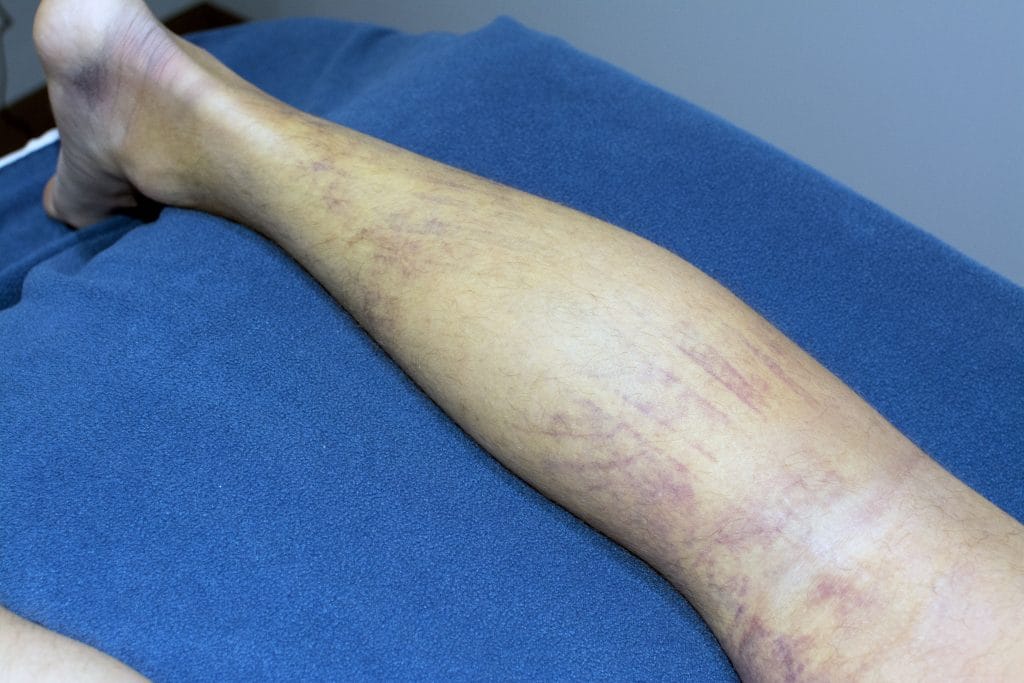

The efficacy of Kinesiology Taping has been debated recently in both scientific literature and social media. In my practice I have found taping to be very beneficial to many patients for numerous different conditions, with the most noticeable and effective being acute (very recent/immediate) injuries. Kinesiology Tape can decrease bruising and pain immediately, with visible results in as little as 24 hours. The following story and images are of a patient whom I was able to treat in the past few weeks. The patient came to the clinic with an incredibly sore and bruised leg. 7 days prior to coming into the clinic, he had been out camping with friends. While lifting a heavy object above his head, he heard a pop and experienced a sudden onset of intense pain down the back of his leg.

An MRI confirmed a hamstring rupture that would need surgery to repair. When a muscle is significantly torn or ruptured, it is common to see massive amounts of bruising as gravity pulls the blood down from the site of the muscle tear and pools it in the lower leg. I treated this patient with laser therapy and kinesiology taping to assist with pain and decrease the amount of bruising in his leg. 30 hours after the first treatment, he returned for a second session. Less visible discolouration was evident wherever I had put tape during his first visit. The intense pain the patient originally felt on the outside of his knee had now diminished, pain was primarily felt in the back of the thigh.

30 hours after applying Kinesiology Tape and two laser sessions.

With daily laser and Kinesiology Taping treatments for the next two days, the bruising and swelling in the patient’s leg significantly decreased. He was able to continue working (albeit not without significant discomfort) until he was able to have the rupture repaired surgically.